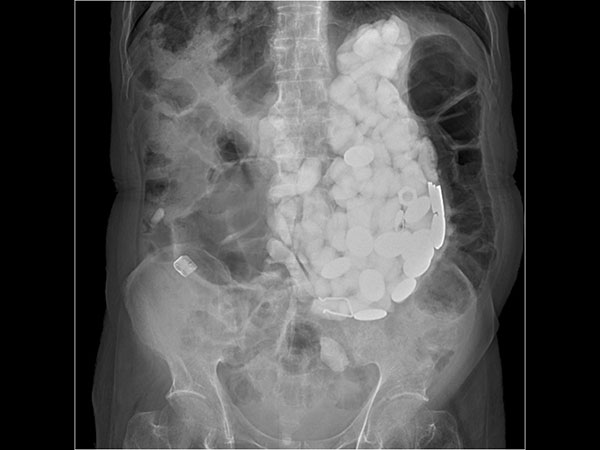

ಇಲ್ಲೊಬ್ಬ ವ್ಯಕ್ತಿಯು ತನ್ನ ಆತಂಕ ನಿವಾರಣೆ ಮಾಡಲು ಕಲ್ಲು, ಬಾಟಲಿಯ ಮುಚ್ಚಳ ಮತ್ತು ನಾಣ್ಯಗಳನ್ನು ತಿಂದಿದ್ದಾನೆ. ಈತನ ಹೊಟ್ಟೆಯಲ್ಲಿ ಸುಮಾರು 2 ಕೆಜಿಯಷ್ಟು ಕಲ್ಲು, ಬಾಟಲಿ ಮುಚ್ಚಳ, ನಾಣ್ಯ ಇತ್ಯಾದಿ ಪತ್ತೆಯಾಗಿದೆ. ಇದನ್ನು ಕಂಡು ವೈದ್ಯರು ಕೂಡ ಬೆಚ್ಚಿ ಬಿದ್ದಿದ್ದಾರೆ. ಕಲ್ಲು, ನಾಣ್ಯ, ಬಾಟಲಿ ಮುಚ್ಚಳ ಇತ್ಯಾದಿಗಳನ್ನು ತಿನ್ನುವಂತಹ ವ್ಯಕ್ತಿಯ ಬಗ್ಗೆ ನಾವು ಈ ಲೇಖನದಲ್ಲಿ ನಿಮಗೆ ತಿಳಿಸಿಕೊಡಲಿದ್ದೇವೆ. ಅದನ್ನು ನೀವು ಓದುತ್ತಾ ಸಾಗಿ...

ಆಸ್ಪತ್ರೆಗೆ ಚಿಕಿತ್ಸೆಗೆಂದು ಬಂದ ವ್ಯಕ್ತಿಯ ಹೊಟ್ಟೆಯು ಉಬ್ಬರಗೊಂಡಿತ್ತು ಮತ್ತು ಹೊಟ್ಟೆಯನ್ನು ವೈದ್ಯರು ಮುಟ್ಟಿ ನೋಡಿದ ವೇಳೆ ಸಣ್ಣ ಸಣ್ಣ ಕಲ್ಲುಗಳು ಪತ್ತೆಯಾಗಿದೆ. ಮತ್ತಷ್ಟು ಪರಿಶೀಲನೆ ನಡೆಸಿದ ವೇಳೆ ವೈದ್ಯರಿಗೆ ಆಘಾತ ಉಂಟಾಯಿತು. ಯಾಕೆಂದರೆ ಆ ವ್ಯಕ್ತಿಯ ಹೊಟ್ಟೆಯೊಳಗಡೆ ಸಣ್ಣ ಸಣ್ಣ ಕಲ್ಲುಗಳು, ಬಾಟಲಿಯ ಮುಚ್ಚಳ ಇತ್ಯಾದಿಗಳು ಕಂಡುಬಂದವು. ಇದು ಸಂಪೂರ್ಣ ಹೊಟ್ಟೆಯನ್ನು ವ್ಯಾಪಿಸಿತ್ತು.

ಈ ವ್ಯಕ್ತಿಯನ್ನು ತಕ್ಷಣವೇ ಶಸ್ತ್ರಚಿಕಿತ್ಸೆ ಮಾಡಲಾಯಿತು ಮತ್ತು ವೈದ್ಯರ ಪ್ರಕಾರ ಇದು ತುಂಬಾ ಕಠಿಣ ಶಸ್ತ್ರಚಿಕಿತ್ಸೆಯಾಗಿತ್ತು. ಯಾಕೆಂದರೆ ಇಂತಹ ಶಸ್ತ್ರಚಿಕಿತ್ಸೆಯು ತುಂಬಾ ಕಠಿಣವಾಗಿರುವುದು ಮತ್ತು ಗ್ಯಾಸ್ಟ್ರೋಸ್ಕೋಪಿ ಮೂಲಕವಾಗಿ ಇದನ್ನು ತೆಗೆಯಬೇಕಾಯಿತು. ಬಾಯಿಯ ಮೂಲಕವಾಗಿ ತುಂಬಾ ತೆಳುವಾದ ಟ್ಯೂಬ್ ನ್ನು ಹಾಕಲಾಯಿತು. ಇದರ ಬಳಿಕ ತುಂಬಾ ಭಿನ್ನವಾಗಿರುವಂತಹ ಶಸ್ತ್ರಚಿಕಿತ್ಸೆ ವಿಧಾನದ ಮೂಲಕ ಹೊಟ್ಟೆಯಲ್ಲಿ ಇದ್ದ ಕಲ್ಲುಗಳು ಹಾಗೂ ಇತರ ಸಾಮಗ್ರಿಗಳನ್ನು ಹೊರಗೆ ತೆಗೆಯಲಾಯಿತು.

ಸುಮಾರು 2 ಕೆಜಿಯಷ್ಟು ಕಲ್ಲು, ಮುಚ್ಚಳ, ನಾಣ್ಯವನ್ನು ಆತ ನುಂಗಿ ಕೊಂಡಿದ್ದ. ವೈದ್ಯರು ತುಂಬಾ ಕಠಿಣವಾಗಿರುವಂತಹ ಶಸ್ತ್ರಚಿಕಿತ್ಸೆ ಮಾಡಿ ಅದರಲ್ಲಿ ಯಶಸ್ವಿ ಕೂಡ ಆದರು. ಆತನ ಹೊಟ್ಟೆಯಲ್ಲಿದ್ದ ಎಲ್ಲಾ ವಸ್ತುಗಳನ್ನು ಹೊರಗೆ ತೆಗೆಯಲಾಯಿತು. ಶಸ್ತ್ರಚಿಕಿತ್ಸೆ ನಡೆಸಿದ ಬಳಿಕ ಸುಮಾರು 9 ದಿನಗಳ ಕಾಲ ಆತ ಆಸ್ಪತ್ರೆಯಲ್ಲಿ ಚಿಕಿತ್ಸೆ ಪಡೆಯಬೇಕಾಯಿತು. ಇದರ ಬಳಿಕ ಆತ ಸಂಪೂರ್ಣವಾಗಿ ಚೇತರಿಸಿಕೊಂಡು ಮನೆಗೆ ಮರಳಿದ್ದಾನೆ. ಆತಂಕ ನಿವಾರಣೆ ಮಾಡಲು ಈಗ ಆತನಿಗೆ ಚಿಕಿತ್ಸೆ ಕೂಡ ನೀಡಲಾಗುತ್ತಿದೆ. ಇಂತಹ ಘಟನೆಗಳು ಆಗಾಗ ನಡೆಯುತ್ತಲೇ ಇರುತ್ತದೆ. ಇದರ ಬಗ್ಗೆ ನಿಮ್ಮ ಅಭಿಪ್ರಾಯ ಹಾಗೂ ಅನಿಸಿಕೆಯನ್ನು ಕಮೆಂಟ್ ಬಾಕ್ಸ್ ನಲ್ಲಿ ನಮಗೆ ಬರೆದು ತಿಳಿಸಿ.